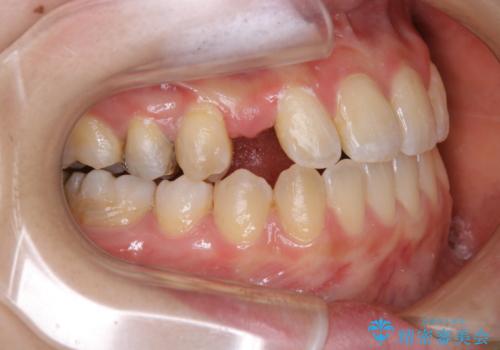

- 受け口で、前歯の嚙み合わせが気になるとの事でご相談にいらした方です。先天的に右上犬歯がなく、左上犬歯も小さい状態でした。矯正治療にて周囲の歯を動かして歯のスペースを確保した上で、被せものにて歯を作っていきました。